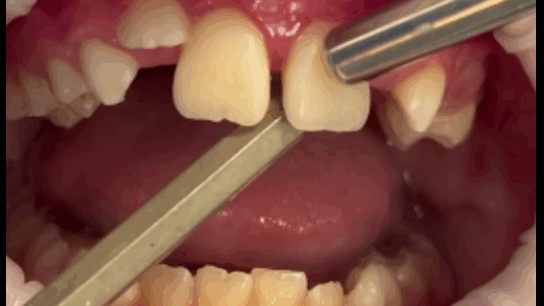

Осмотр полости рта: зубы 5.3, 6.3 прорезаны полностью, коронка интактная, подвижность отсутствует, зуб 1.2 в стадии прорезывания, имеет вестибулоположение, коронка интактная, подвижность отсутствует, зуб 2.2 в полости рта не прорезался. Зуб 6.4 в полости рта отсутствует, зуб 6.5 коронка интактная, подвижность отсутствует. Зубы 1.1, 2.1: визуализируется диастема, коронки зубов интактные, в цвете не изменены, патологическая подвижность 2 степени, перкуссия болезненная. Холодовая проба: положительная кратковременная реакция. При зондировании пародонтологическим зондом (вестибулярно и нёбно в трех точках) определяются патологические зубодесневые карманы глубиной до 13 мм. Гнойное отделяемое отсутствует. Краевая слизистая в области зубов 1.1, 2.1 гиперемирована. Фенотип десны во фронтальном отделе верхней челюсти толстый (Рисунки 1-3)

Рисунок 3. Определение подвижности зубов (анимация).